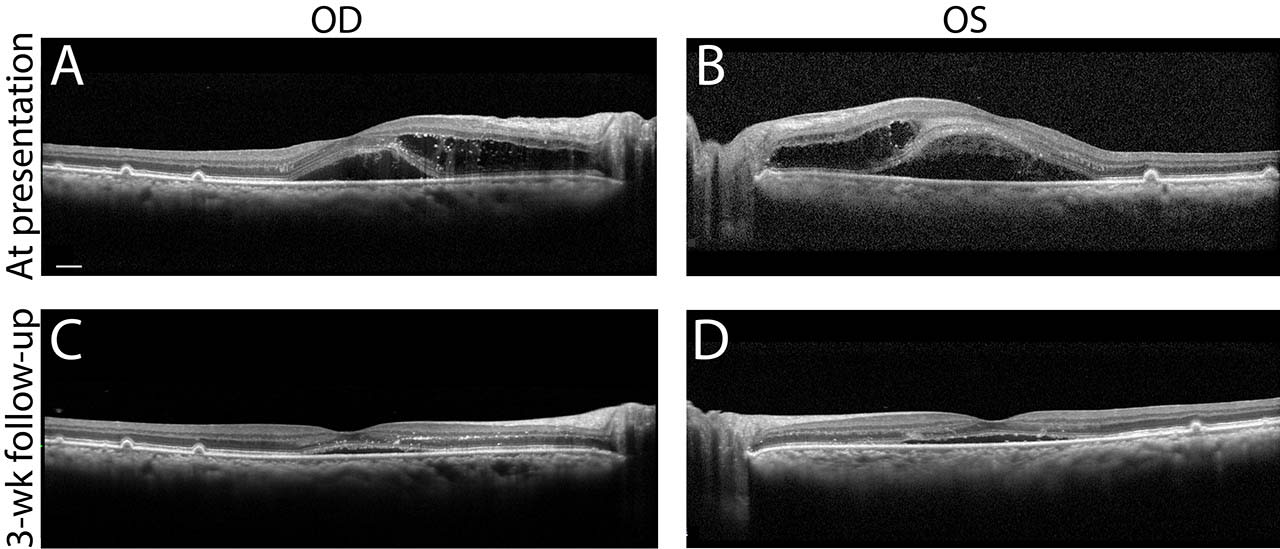

Her visual acuity was 20/60 in the right eye and counting fingers at 3 feet in the left eye. Intraocular pressures were normal, visual fields by confrontation were generally full, and pupils were equal and reactive bilaterally. Fundoscopy showed bilateral disc edema, tortuous vessels, sizable cotton wool spots, intraretinal hemorrhages, and hard exudates tracking along the inferior arcades (Figure 1, A and B). On optical coherence tomography (OCT), a large amount of subretinal and intraretinal fluid was noted, extending from the disc and into the macula (Figure 2, A and B).

Three weeks later, the patient’s vision had improved to 20/25 in the right eye and 20/40 in the left eye. Fundoscopy showed significant improvement of hemorrhages, smaller exudates, and reduced disc edema (Figure 1, C and D, white arrows). Substantial reduction in subretinal and intraretinal macular fluid was observed on OCT (Figure 2, C and D). Fluorescein angiography showed delayed choroidal flush with stippling and leakage from the optic disc. Close follow-up without ocular intervention was recommended and the patient was encouraged to follow up with both her primary care provider and an endocrinologist. An adrenal mass was later identified, and the patient was diagnosed with primary hyperaldosteronism. Her disease was medically managed, but she ultimately developed end-stage renal disease and passed away ~2 years after initial presentation.